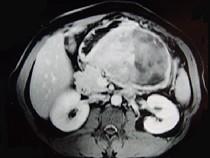

问题 男,36岁,腹胀、消化不良、消瘦、中上腹痛,影像检查如下图,最可能的诊断是()

选项 A.胃间质肉瘤并肝转移 B.胃间质瘤并原发性肝癌 C.内胚窦瘤肝转移 D.胃淋巴瘤伴原发性肝癌 E.胃间质瘤并肝血管瘤

答案 A